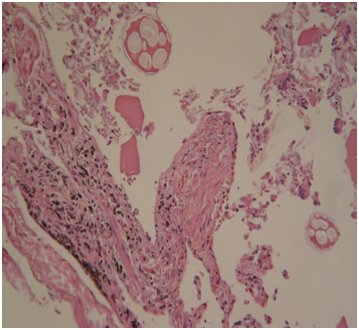

Histology: Acute emphysema was the prominent observation; edema and hemorrhages were also present.4 In 9 cases (Figures 3-6), exogenous material in the airways, comprehensive of planktonic boli in the lower branches, clearly demonstrable at polarization microscope (and possibly confirmable at SEM’s elemental analysis with EXD). Zoo- and phytoplankton have been better identified in the UV microscope. It is mandatory to differentiate the planktonic material from gastric content, regurgitated and aspirated (Figure 7 & 8).

Figures 3,4 Drowning in seawater. Images of endoalveolar zooplankton (protoconch of crustacean) (EE, 480 X, polarized light).

Figure 5 Drowning in freshwater; recovery corpse in the sea after 20 days. Endoalveolar phyto- and geoplankton (EE, 240X, polarized light).

Figure 6 Drowning in freshwater; recovery corpse after few hours. Geo- and phytoplankton in a lower bronchus (EE, 120X, polarized light).